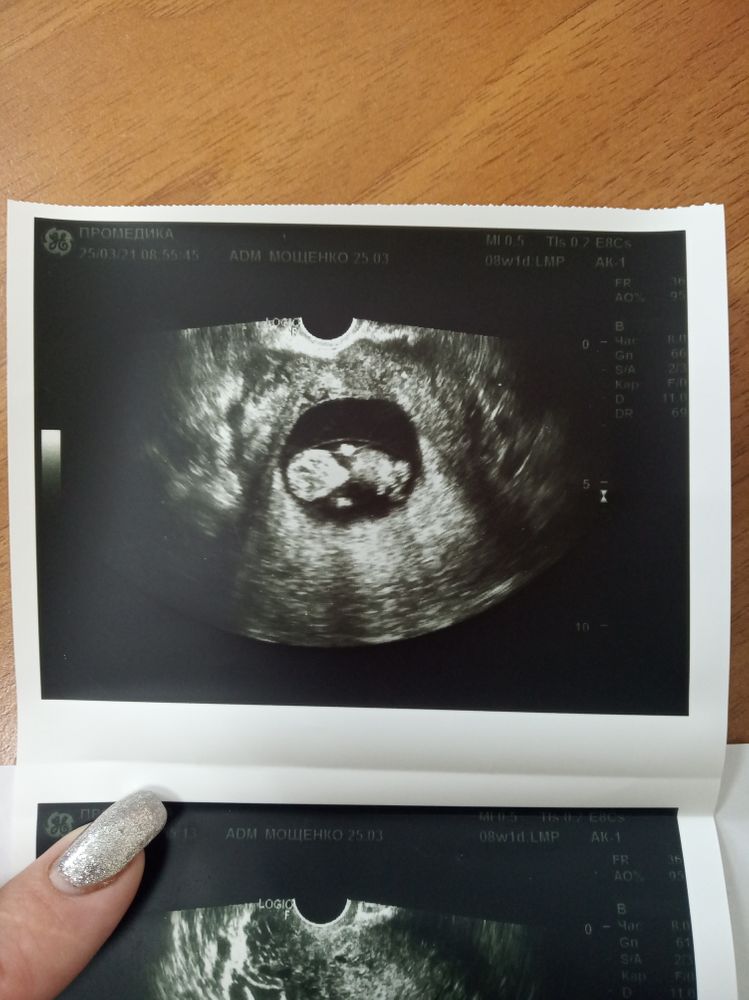

Всё о нашей беременностиСовсем не чувствую себя что беременна, только грудь болит,не удержалась пошла на узи🤭по УЗИ нам 10/4.

Поздравляю Вас) Прекрасные узи)))